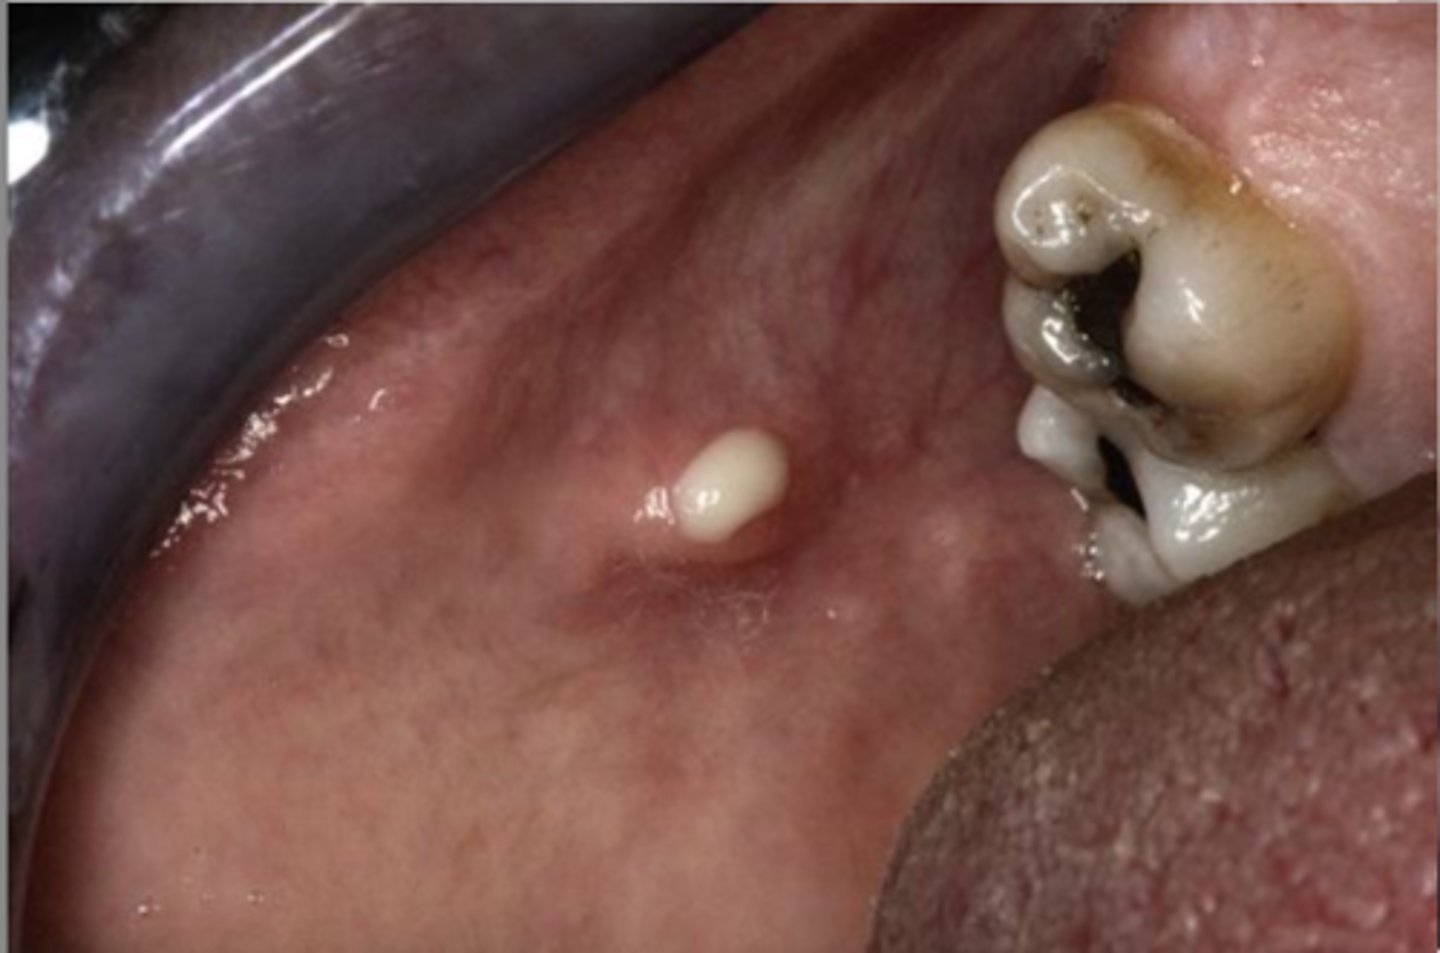

Salivary Duct Cyst

Mimic mucoceles in

appearance

Major and minor salivary glands

Where is the site for Salivary Duct Cyst?

Ranula

Resembles frogs

underbelly, Less common type of mucocele

sublingual, submandibular gland

a ranula involves which gland?

Plunging Ranula

Dissects through mylohyoid

▫ Swelling in the neck

Marsupialization, Removal of feeder gland

What are some treatments for Ranulas?